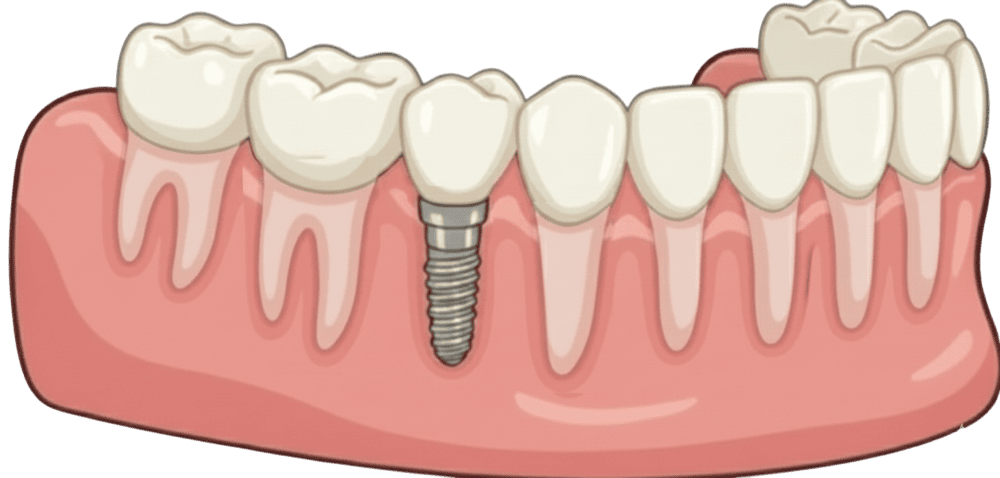

(Single Implant)

Even a perfectly placed implant can look artificial if the surrounding gums aren’t appropriately managed. Common issues with poor soft tissue management:

❌ Metal showing at the gumline

❌ Uneven gum heights

❌ Tissue recession

❌ Red or black tissue colour

❌ Unnatural contours

✅ Pink, healthy gums that match your natural teeth in color and texture

✅ Proper gum height and contours

✅ Prevents gum recession and metal show-through

✅ Natural look growing

✅ Protects implant from bacteria and bone loss

Implant Placement using surgical guides for precision, the titanium implant is placed into your jawbone, typically 30-60 minutes with local anaesthesia.

Once healed, we attach the custom crown, your new tooth that looks, feels, and functions naturally.